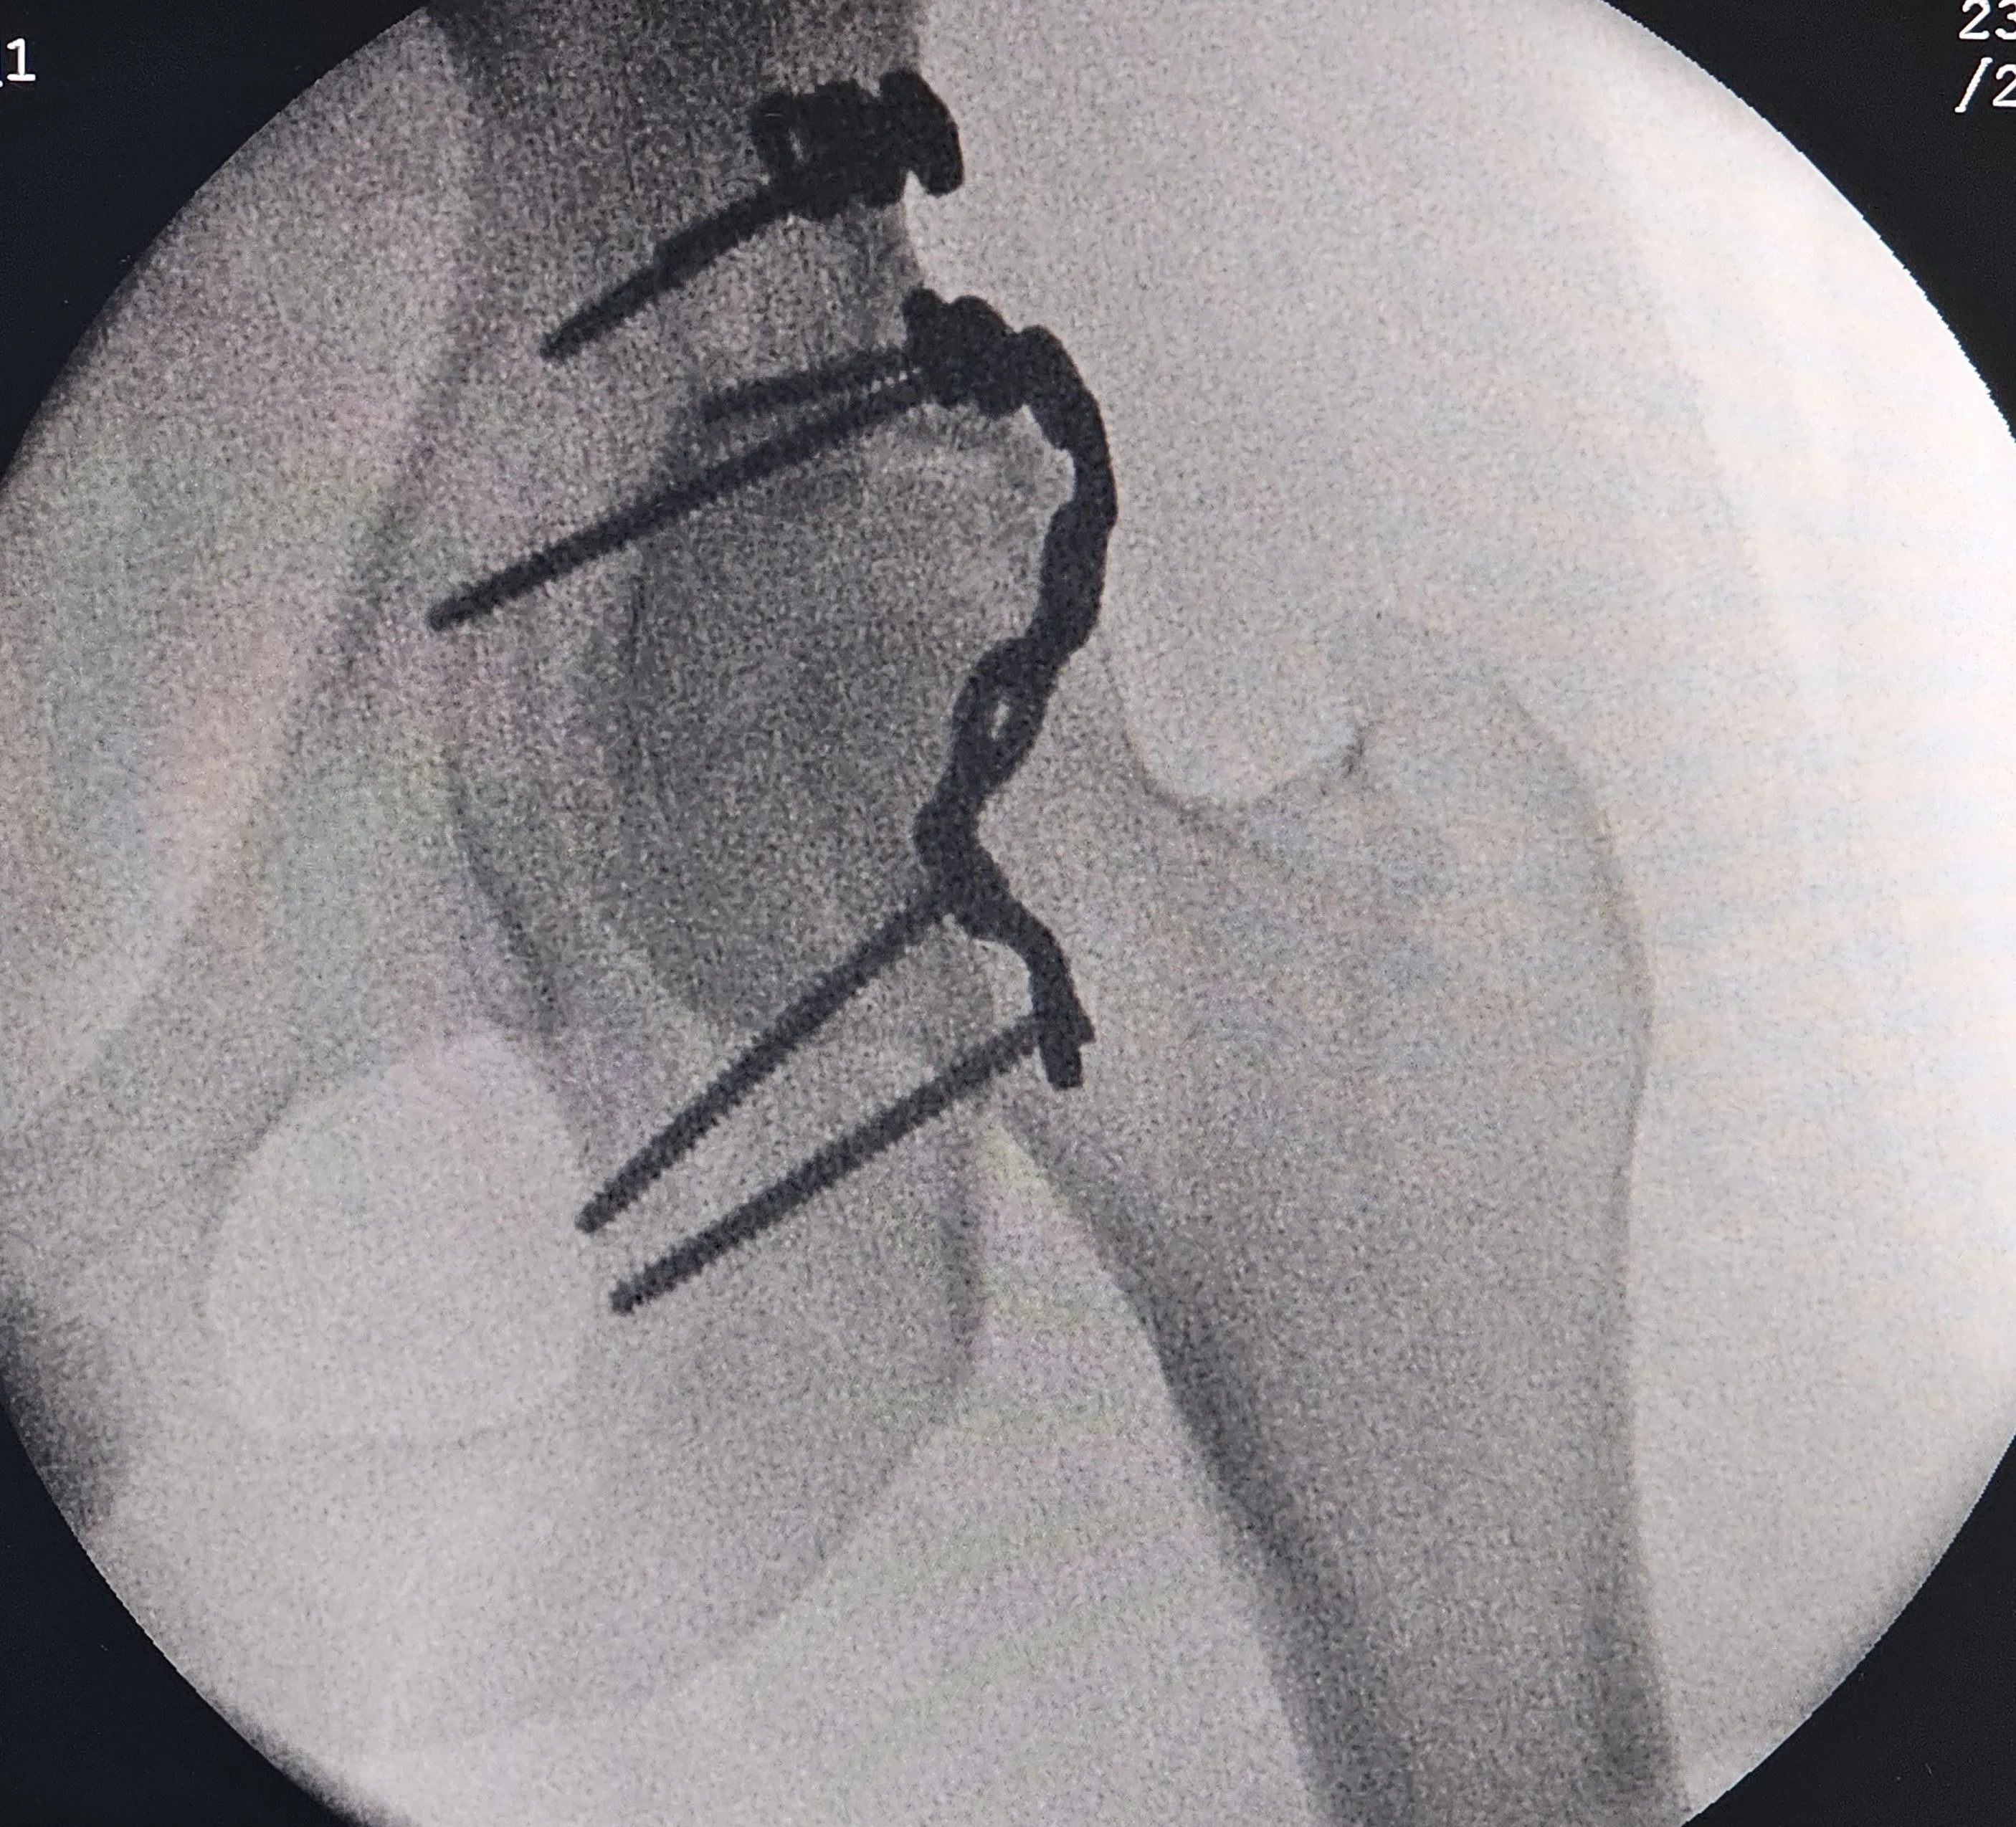

- Fixação Provisória e Moldagem da Placa: Domine a técnica de introdução do afastador inferior na incisura isquiática menor após descolamento cuidadoso. Realize a fixação provisória dos fragmentos com fios de Kirschner. Utilize alumínio para moldar um modelo da placa, que será usado para a confecção de um molde definitivo da placa de fixação.

- Fixação Definitiva com Múltiplas Placas: Aprenda a fixar a placa principal no ísquio, contornando todo o rebordo posterior, com parafusos direcionados para o teto acetabular. Utilize uma segunda placa no vértice do fragmento superior para fixação. Compreenda como a utilização dessas duas placas proporciona redução e estabilidade satisfatórias, eliminando a necessidade de placas em mola.